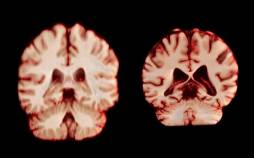

دانشمندان در کنفرانس انجمن بین المللی آلزایمر (AAIC) سال ۲۰۱۹ اعلام کردند: زنانی که در سنین پایین شاغل میشوند خطر ابتلا به آلزایمر در آنها کاهش میی

[ادامه]

پژوهش ها نشان می دهد؛ پژوهش جدیدی که توسط گروهی از روانپزشکان به انجام رسیده نشان می دهد خردسالانی که دچار افسردگی می شوند، ممکن است سالها بعد نیز دوباره با این اختلال روب